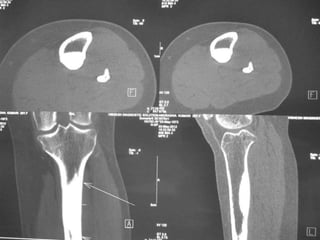

• Excision of the osteoid osteoma nidus using

CT–assisted localization, a Kirschner wire

inserted into the nidus, and a biopsy punch

inserted over the Kirschner wire into the

bone.

• They recommend using a trephine 2 mm

larger than the lesion for complete removal.

• A CT guided needle was passed to localize the

lesion.

• Through an anterior "Hernia" approach the

lesion was approached and excised.

• The Follow-up CT Scanning done to reveal

complete removal of lesion.

• A biopsy confirmed it later.

Osteoid Osteoma -Tx • Excision of the osteoid osteoma nidus using CT–assisted localization, a Kirschner wire inserted into the nidus, and a biopsy punch inserted over the Kirschner wire into the bone. • They recommend using a trephine 2 mm larger than the lesion for complete removal. • Recurrence after apparently complete excision has been reported but is rare.

• A CTguided needle was passed to localize the lesion. • Through an anterior "Hernia" approach the lesion was approached and excised. • The Follow-up CT Scanning done to reveal complete removal of lesion. • A biopsy confirmed it later.